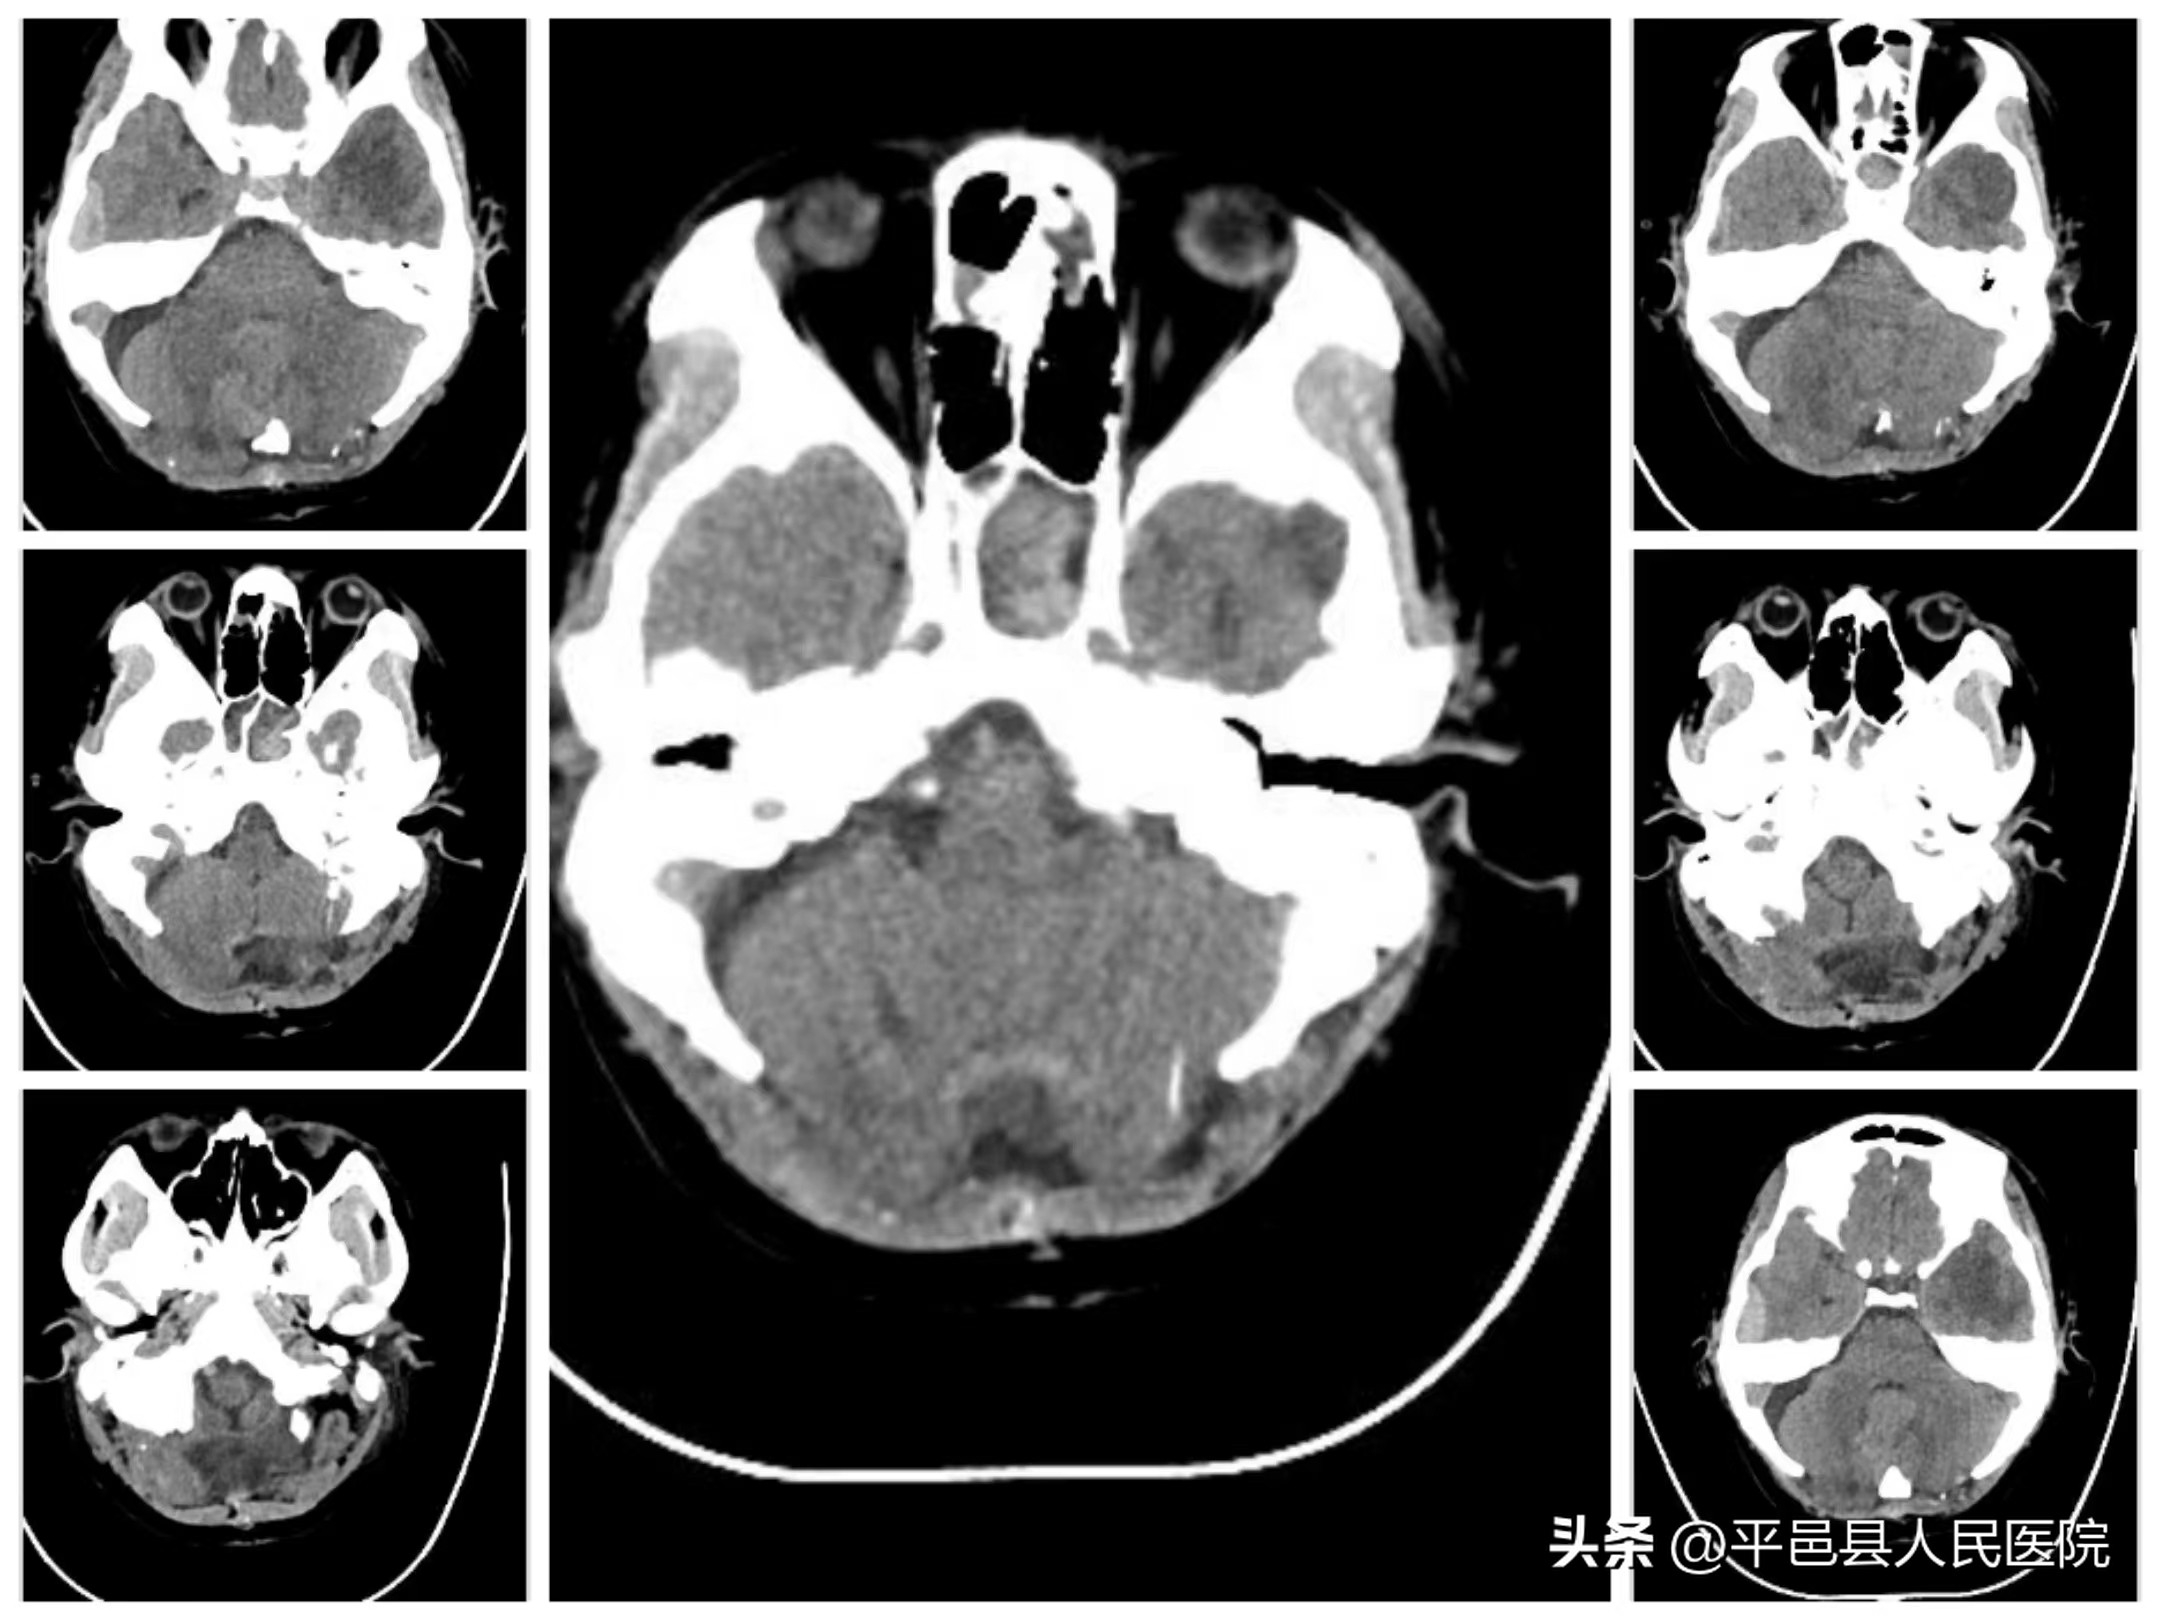

随后多发性小脑挫裂伤、小脑血肿、枕骨凹陷、粉碎性骨折由神经外科二病区紧急行小脑血肿清除、枕骨粉碎骨折清除减压手术,同时给予输血、补液纠正休克,手术顺利完成。术后转入神经外科二病区继续治疗额颞叶多发大脑挫裂伤、硬脑膜下血肿、硬膜外血肿。

术后颅脑CT示血肿清除